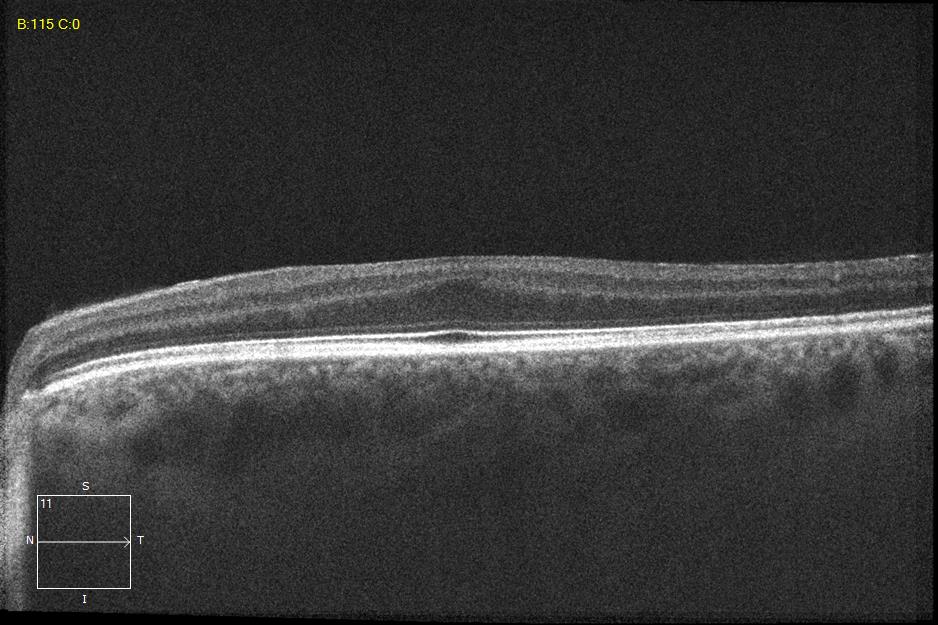

Two different patients with isolated foveal hypoplasia grade 2. The definitions of fovea plana and foveal hypoplasia have led to controversy among experts. The term fovea plane refers to the anatomical absence of a foveal pit. An estimated 3% of children with clinically normal eyes have an underdeveloped foveal pit on OCT. According to some experts, a foveal pit is not absolutely necessary for foveal cone specialization. A diagnosis of fovea plana alone does not automatically herald functional disability. It is possible to maintain adequate visual acuity in an eye with a fovea plana. Foveal hypoplasia refers to an underdeveloped fovea with vision loss. Foveal hypoplasia has also been seen in conditions such as aniridia, albinism, achromatopsia, nanophthalmus, and incontinence. pigment and premature retinopathy.

In contrast to other definitions, Thomas et al. defined foveal hypoplasia as the persistence of inner retinal layers in the fovea and developed a grading system based on optical coherence tomography features. According to this grading system, grades 2, 3, and 4 of foveal hypoplasia corresponded to the fovea plana.

Grade 2 foveal hypoplasia has all the features of grade 1, except that there is no pit.